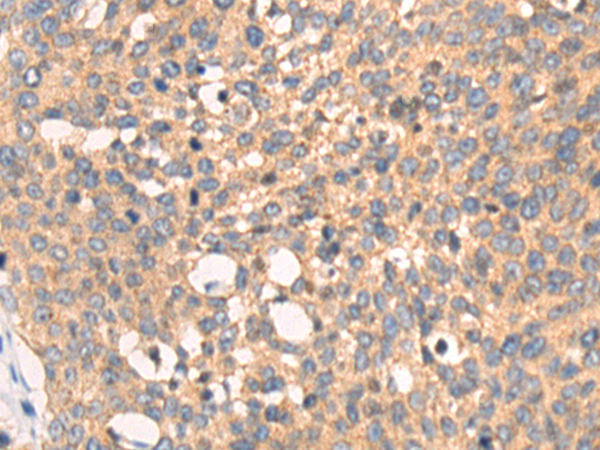

分类: 科研抗体货号: P00198别名: ASP2; BACE; HSPC104应用: WB,IHC反应种属: Human, Mouse, Rat